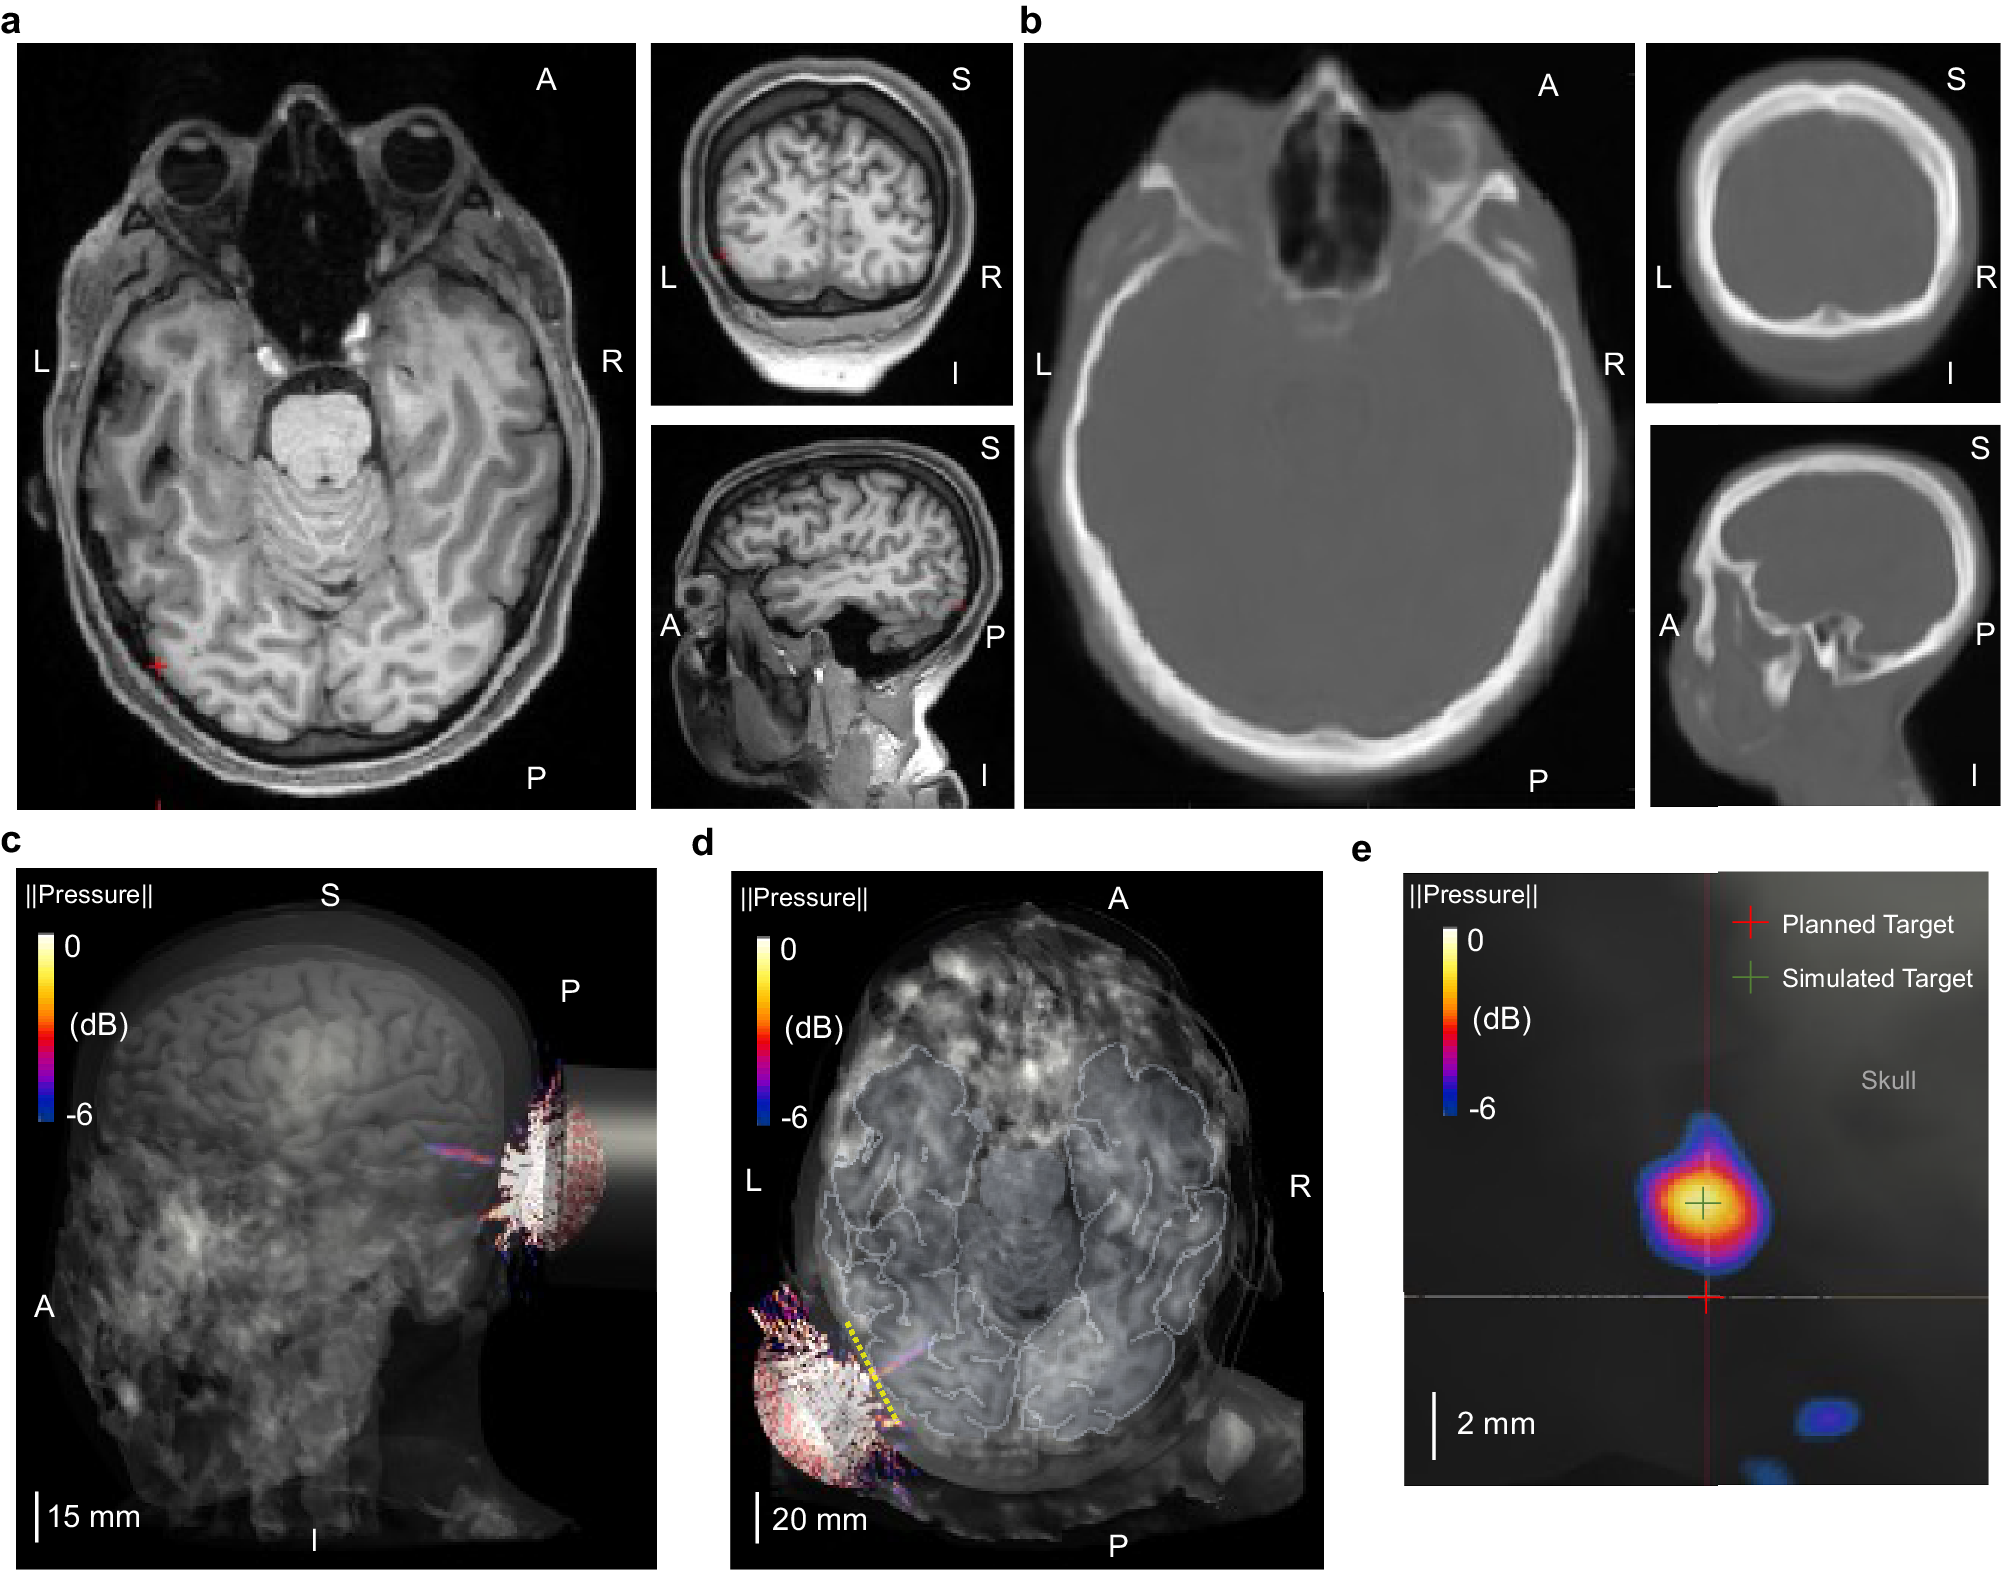

Fig. 5: Computer simulations of tFUS generated by the 128-element random array ultrasound transducer in a representative individual (Subject #5).

a The subject-specific T1-weighted structural magnetic resonance images in horizontal, coronal and sagittal planes, with the red cross indicating the geometrical center of the V5 area. b Pseudo-CT images generated from the MRI in the same imaging planes as illustrated in a. c, d The transcranial pressure field and focused ultrasound beam (−6dB focal pressure volume) co-registered with the subject skull and brain models. e A lateral view of the transcranial ultrasound focus (−6dB focal pressure volume) on the surface of V5 along the yellow dashed line in d. The center of planned target used for optical-based brain navigation is depicted using a red cross, while the center of simulated ultrasound target is at the location marked with a green cross. The deflection of ultrasound focal spot is quantified with the spatial distance between these two crosses, which is measured as 2.84 mm for this subject. Extensive subject-wise characterizations of transcranial ultrasound focus are depicted and listed in Supplemental Fig. S3 and Supplemental Table S1.